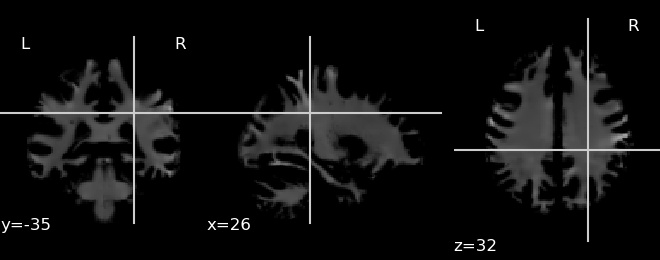

To understand which regions of the brain are important in the decision making process we perform a slightly modified version of occlusion analysis proposed in [30] to fit our data. In this analysis, usually a part of the scan is occluded with gray or white patch and the output from the network is recalculated. The occluded region is considered to be important if the probability of the target class decreases compared to the original image. The heatmap of relevance is calculated by sliding the patch across the image and plotting the difference in the probability. In our case we repeated the procedure twice, once for each of the GM and WM images. The resultant heatmaps are presented in Fig. 5, where the important areas are marked in red.

![]() |

| (a) Heatmap for White Matter |

| (b) Heatmap for Gray Matter |

To better understand the above heatmaps we also calculated the relevance per brain area using methods provided by [30] which is presented in Fig. 7 and Fig. 7. We can see for Gray Matter the most focused on area is Superior Frontal Gyrus and for White Matter it is Postcentral Gyrus.